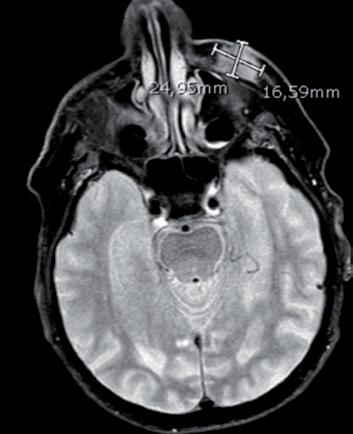

La prima paziente inserita in EAP era una donna di 87 anni, ECOG PS 2, portatrice di un voluminoso aCSCC della guancia sinistra con infiltrazione della palpebra inferiore, dell’ala nasale e dell’arco zigomatico ed esposizione del seno mascellare omolaterale (figura 6A). La paziente ha iniziato cemiplimab

a giugno 2019, ottenendo subito un’ottima risposta ed arrivando a risposta completa clinica a febbraio 2020 (figura 6B). La risposta completa è tuttora persistente (figura 6C), nonostante una pausa di 3-4 mesi concessa alla paziente nel periodo di massima incidenza della covid-19. Il secondo caso riguarda una donna di 83 anni, ECOG PS 2, con un voluminoso aCSCC in regione pre-auricolare destra. La paziente era notevolmente sintomatica per dolore, per anemizzazione da sanguinamento (Hgb fino a 5 g/dl, con necessità di trasfusioni) e per difficoltà nell’alimentazione (figura 7A). Cemiplimab è stato iniziato ad agosto 2020 ottenendo, dopo due sole somministrazioni, un’iniziale risposta con netta riduzione dei sin-